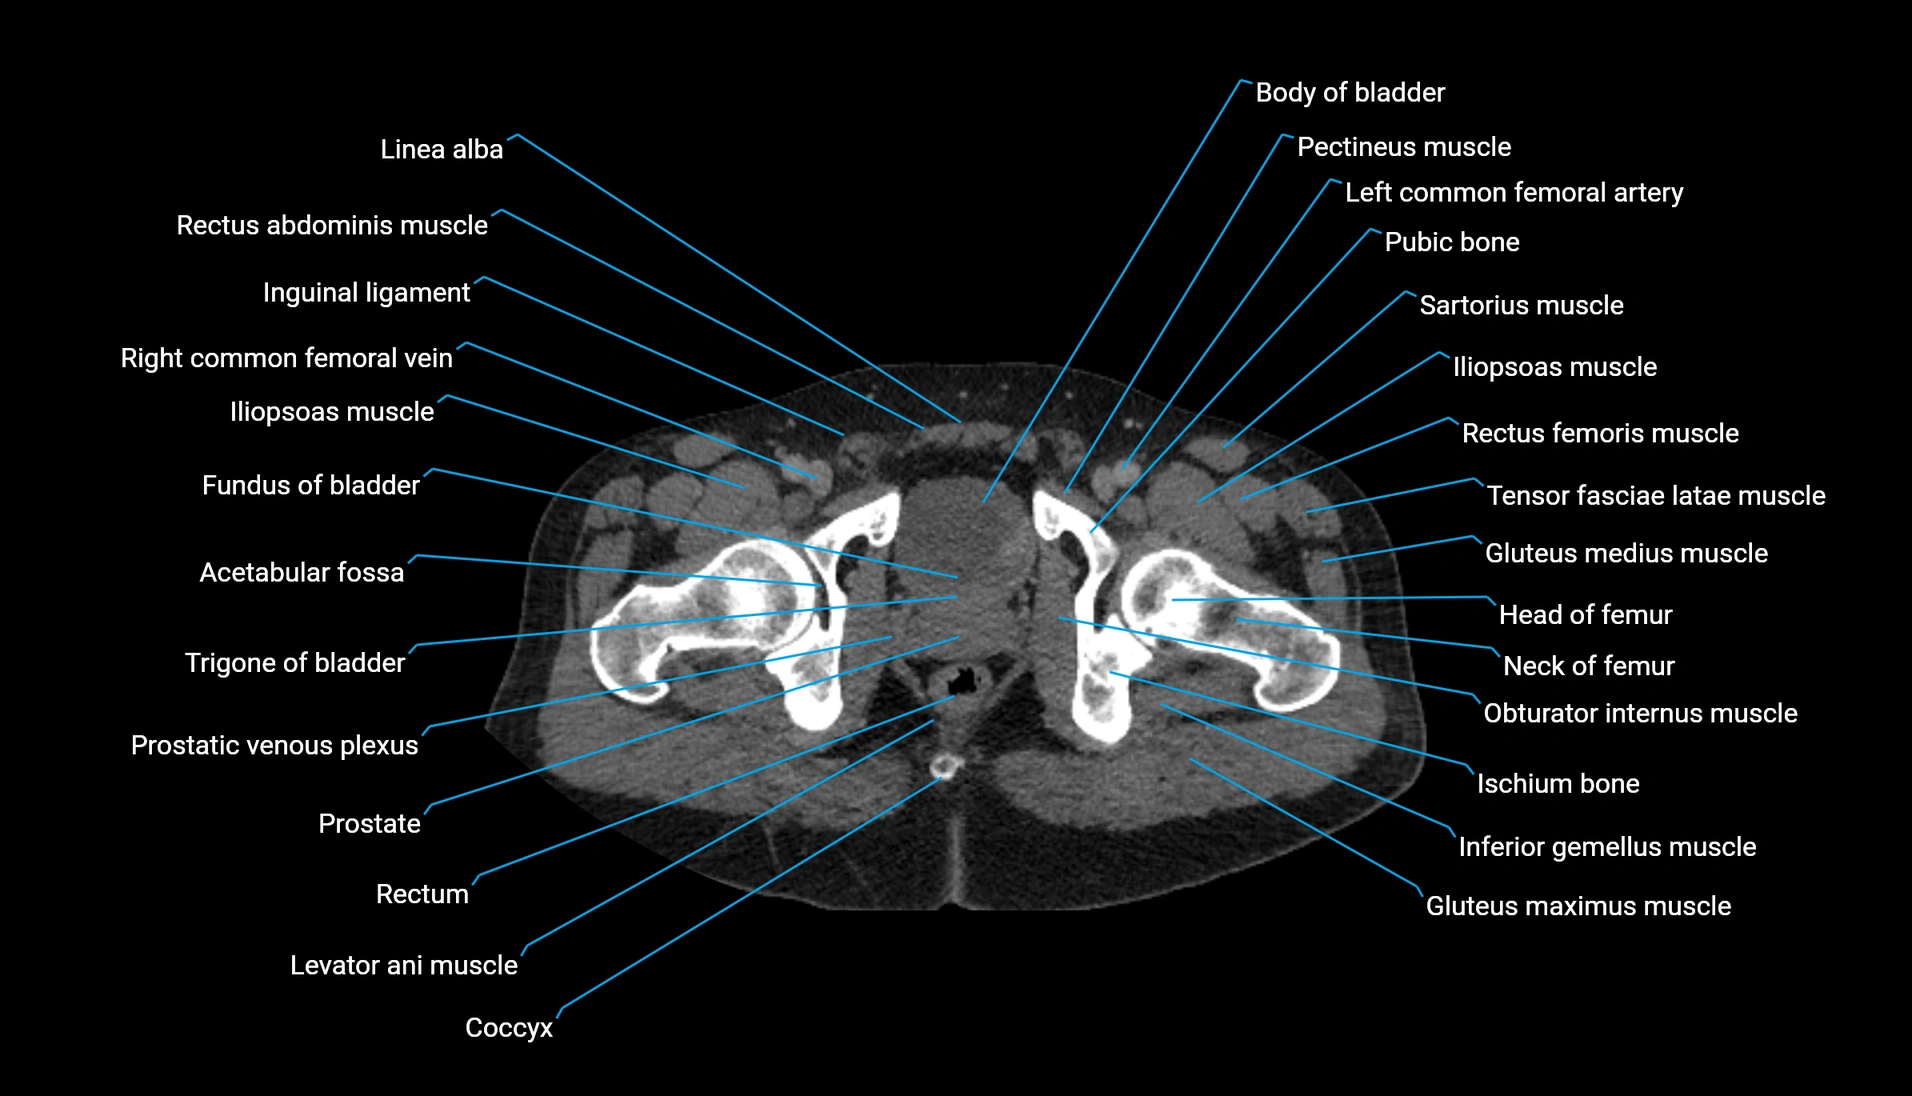

CT Appearance

Non-contrast CT:

-

Demonstrates cortical bone of acetabular rim in excellent detail

Detects fractures, dysplasia, retroversion, or bony overcoverage (pincer impingement)

3D reconstructions used in preoperative hip surgery planning

CT Post-Contrast (CT Arthrography):

Joint contrast outlines the acetabular labrum, cartilage, and margin

Demonstrates labral tears, cartilage defects, and subtle bony abnormalities

Alternative to MR arthrography in patients with MRI contraindications

CT VRT 3D image

CT image